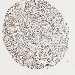

CANCER BREAST CANCER Show tissue menu

BRCA TCGA BRCA VALIDATION PROTEIN EXPRESSION